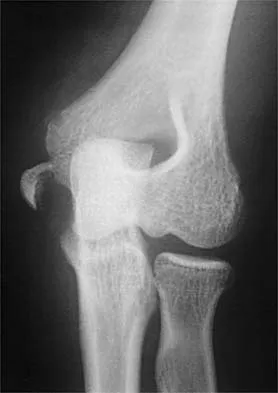

Figures 5a and 5b show the radiographs of an 11-year-old boy who felt a pop and immediate pain in his right knee as he was driving off his right leg to jam a basketball. Examination reveals that the knee is flexed, and the patient is unable to actively extend it or bear weight on that side. There is also a large effusion. Management should include

Explanation

Fractures through the cartilage on the inferior pole of the patella, the so-called sleeve fracture, are often difficult to diagnose because of the paucity of ossified bone visible on the radiographs. If the fracture is missed and the fragments are widely displaced, the patella may heal in an elongated configuration that may result in compromise of the extensor mechanism function. The treatment of choice is open reduction and internal fixation using a tension band wire technique to achieve close approximation of the fragments and restore full active knee extension. Heckman JD, Alkire CC: Distal patellar pole fractures: A proposed common mechanism of injury. Am J Sports Med 1984;12:424-428.